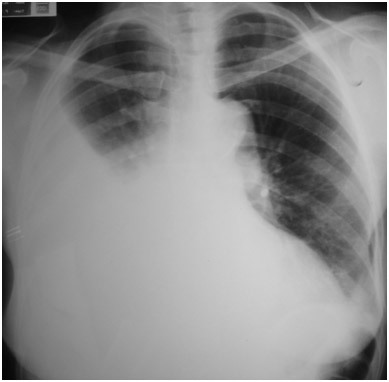

Paciente vitima de trauma de tórax apresenta-se na emergencia com MV diminuidos ou abolidos, hipertimpanismo, desvio da traqueia para o lado contralateral, turgencia jugular e hipotensão…

Diagnóstico, exame de imagem, conduta imediata e definitiva?

PNEUMOTÓRAX HIPERTENSIVO

Não fazer exame de imagem. Diagnóstico é clínico

Conduta imediata

Toracocentese de alívio no 4-5o EIC anterior a linha axilar media

*na criança continua no 2o EIC

Conduta definitiva

Drenagem em selo d’água (toracostomia) no 5o EIC anterior a linha axilar media